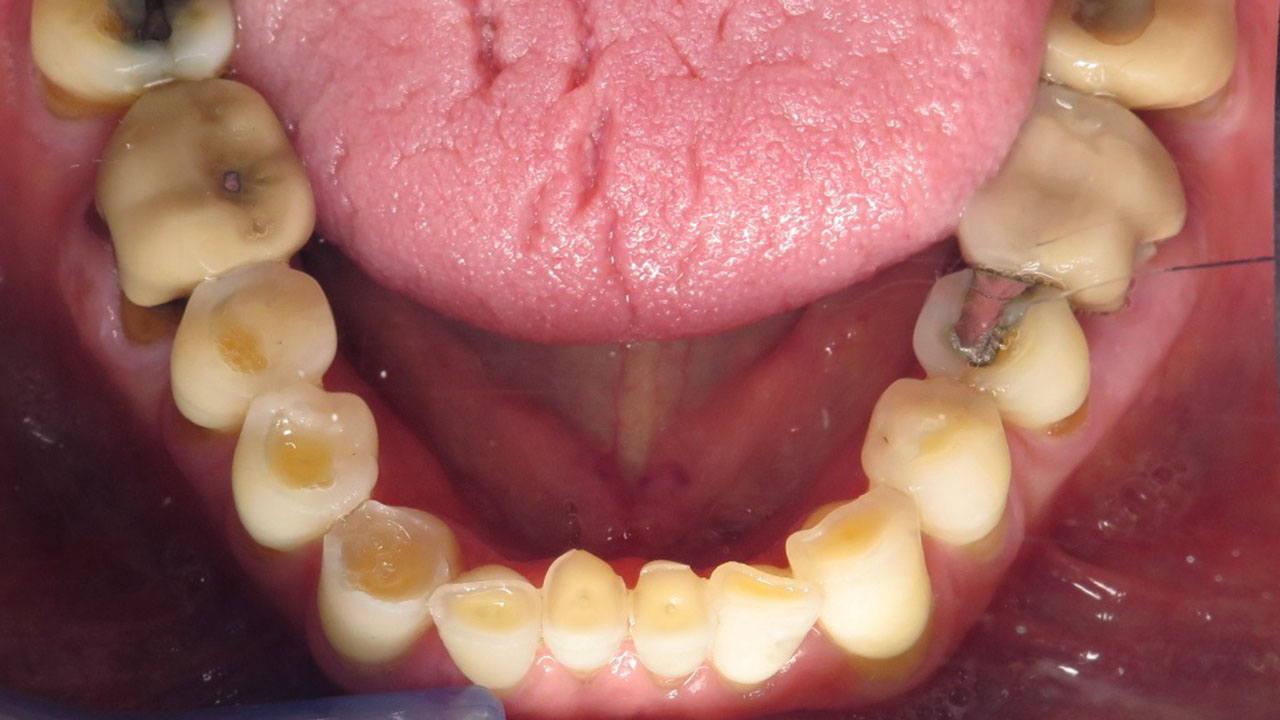

The patient was referred by his periodontist after being told that severe tooth grinding had worn his teeth down significantly and that he could lose his teeth if he did nothing to restore them.

Hopeless lower teeth were removed and the remaining teeth were restored with all-ceramic crowns to rebuild the bite and protect the worn dentition.

- Removal of hopeless mandibular posterior teeth

This patient was referred by his periodontist after severe tooth grinding had worn his teeth down significantly. He had already lost several teeth, and the remaining lower back teeth had a poor long-term prognosis if the bite was not restored.